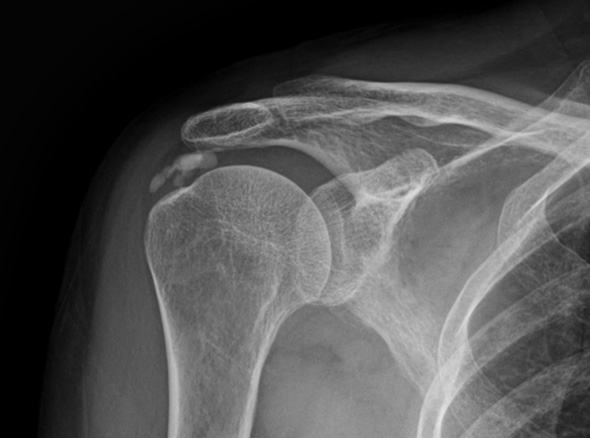

수술적 치료

관절 내시경을 통한

석회제거술

내시경을 통하여 석회를 직접 보며,

힘줄 손상을 최소화시켜 석회 및 염증을 제거합니다.